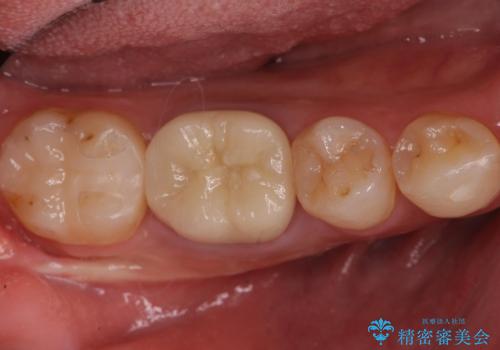

- 右下6 精密根管治療(大臼歯・リトリートメント):143,000円 土台:22,000円 仮歯:11,000円 ジルコニアクラウン:121,000円 合計297,000円費用は治療当時の料金となります

治療後は症状も改善し、半年後の経過も良好です。